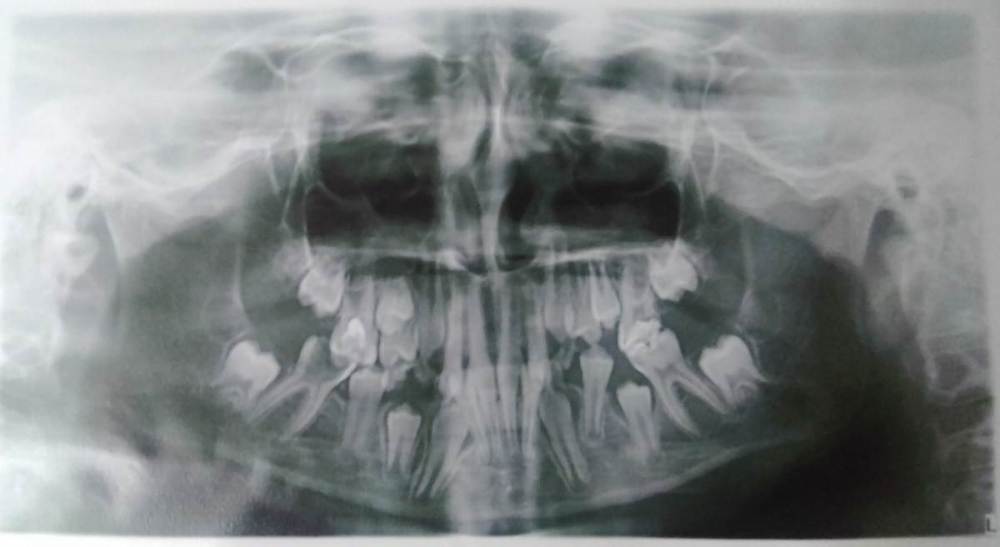

Зуб нижняя шестерка первый раз лечили полгода назад в детской стоматологии туда же обратились повторно сразу сказали что если заболит или опухнет десна то лишь удалять... очистили полость зуба 24 марта 2023г. сказали полоскать с содой солью на период еды вставлять в полость ватку так мы делали до 30 марта 30 марта как и сказал врач пришли на прием и поставили временную пломбу записаться сказали на 6-7 апреля. записались на 6 апреля.. сегодня 3 го апреля к вечеру ребенок стал жаловаться что зуб снова болит.... Ясно что нужно идти к стоматологу но есть ли методы лечения и сохранения постоянного зуба в данной ситуации?

На снимке это зуб сразу после удаления первой пломбы врач посмотрев снимок сказала что у корня видно воспалительный процесс то из за него возможно и удалять придется..

По снимку зуб можно (и нужно) лечить. А также показаться ортодонту - с другой стороны нет места для прорезывания пятого зуба.